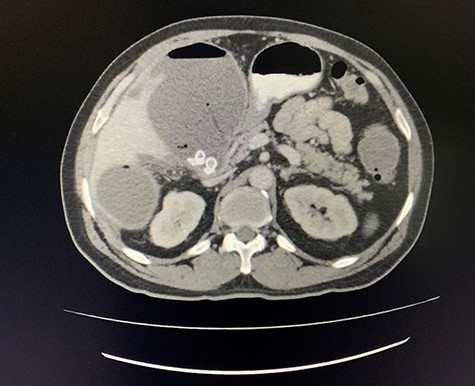

A computed tomography (CT) scan of the abdomen revealed an enlarged, thickened gallbladder with multiple stones, communicating with an intrahepatic collection in segment 4 measuring 116 × 80 mm, with an associated air fluid level and air locules (Fig. 1). There was an apparent fistulous tract to the hepatic flexure of the colon, another large collection in segment 6 (97 × 96 mm) as well as other smaller collections (Figs 2 and 3).

Axial view of portovenous phase of CT scan of the abdomen demonstrating enlarged, thickened gallbladder with radio-opaque gallstones with apparent fistulous communication with the hepatic flexure of the colon with associated pneumobilia.